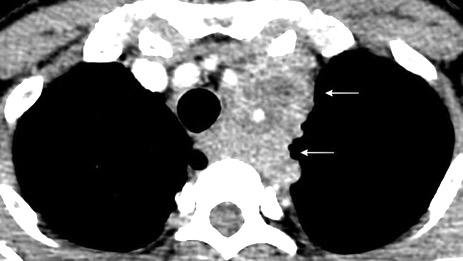

Fenómeno compensatorio por función insuficiente de médula ósea.

Mielofibrosis. Policitemia vera. Leucemia Linfoma.

Post-irradiación de médula ósea. Anemias hemolíticas. esp. Talasemia intermedia/ minor)

Haidar R. Paraspinal extramedullary hematopoiesis in patients with thalasemia intermedia. Eur Spine 2010

Lesiones inactivas “viejas”: alta intensidad de señal en T1 y T2. (infiltración grasa) Depósito de hierro: Baja intensidad de señal en T1 y T2

RM: Hipo intensidad de señal. Hemosiderosis secundaria. ¡Hígado! Haidar R. Paraspinal extramedullary hematopoiesis in patients with thalasemia intermedia. Eur Spine 2010